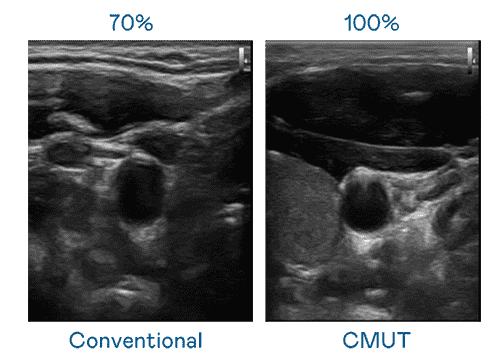

CMUT 技术是一种用电容式微机电元件来产生超音波讯号的技术。。。。与传统 PZT 压电式技术相比,,CMUT 频宽增加 30%,,,,更宽频的超音波讯号让影像解析度大幅提升,,,,是实现高影像品质医疗超音波扫描、、、、促进精准医疗发展的关键技术。。。

超音波影像的解析度高低,,,,首先取决于探头能发出的讯号频宽。。。。菠菜论坛 CMUT 可提供高清晰的超音波讯号,,,,提供高频宽、、、高灵敏度、、影像纹理细节更高的超音波影像,,,,协助医护人员缩短影像判读时间及利用精准的医疗影像进行诊断。。。。